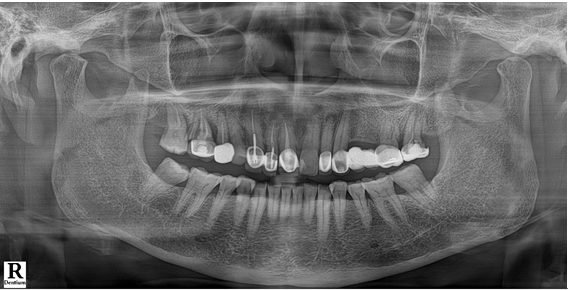

전치부는 지르코니아, 구치부는 보험임플란트 pfm 으로 제작 (70세 여자)

c.c: 앞니가 부러졌고, 오른쪽 어금니가 아파요.